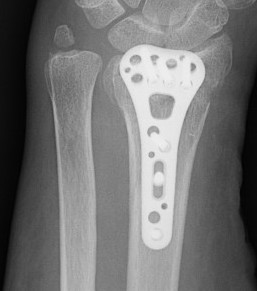

Complications of surgery

Nwosu et al J Hand Surg Am 2023

- systematic review of 1400 patients treated with volar locking plates

- 12% major complication

- median nerve injury 7%

- hardware removal 7%

- tenosynovitis 3%

- CRPS 2%

- malunion 1%

- infection 2%

- tendon rupture 1%

Tendon rupture

Azzi et al Plastic Reconst Surg 2017

- systematic review of tendon rupture after surgery

- 56 studies and 6000 patients

- volar plates: tendon rupture 1.5%, tenosynovitis 4.5%

- dorsal plates: tendon rupture 1.7%, tenosynovitis 7.5%